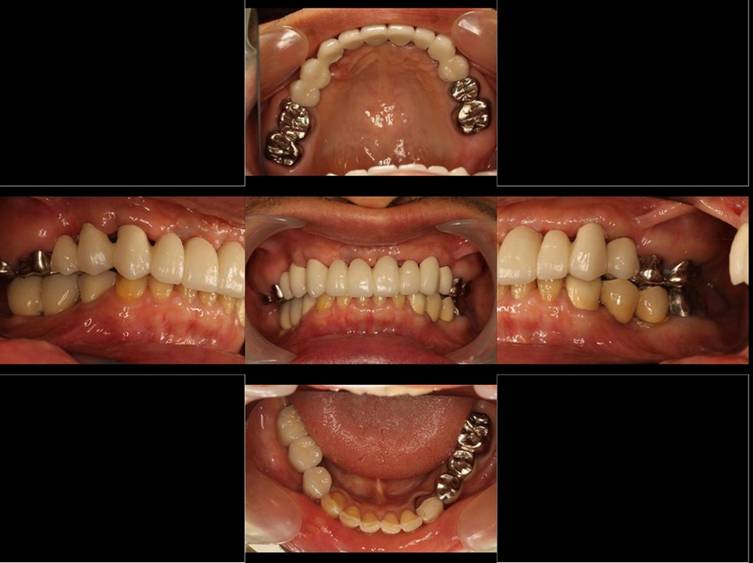

上部構造装着後6年。ハイブリッドレジンを使用したため、少し艶がなくなってきました。上部構造の材料には金属、ハイブリッドレジン、セラミックなどがあります。セラミックはきれいですが欠けやすいため、最近はフルジルコニアを使っています。

上顎 少しすり減ってきました。

下顎。12か月に一度メインテナンスをしています。

インプラント装着後6年。順調に経過しています。12か月毎のメインテナンスをしています。